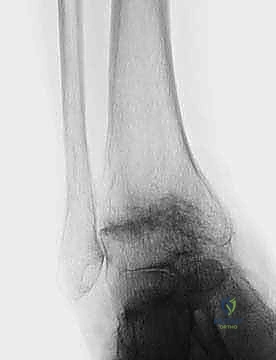

FIG 6 • The TNK ankle replacement for rheumatoid arthritis of the ankle (cemented replacement). A. Preoperative AP view. B. Preoperative lateral view. C. Postoperative AP view 2 years 6 months after the surgery. D. Postoperative lateral view.